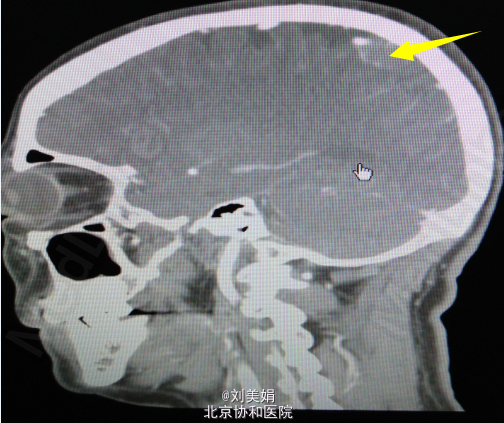

头增强CT:平扫图象显示:左侧顶部见一圆形略高密度影,边缘光整,边界清晰,大小约28.2mm×23.7mm,CT 值 68.2Hu,其内未见钙化,周围脑回受压、塌陷,脑室系统无扩大,脑沟裂未见增宽。中线结构未见明显移位。 增强图象显示:病灶明显均匀强化。CT 值为 92Hu,密度均匀,边缘清晰。右侧筛窦密度增高。

左顶部颅内占位性病变 神经导航下开颅窦旁脑膜瘤切除术